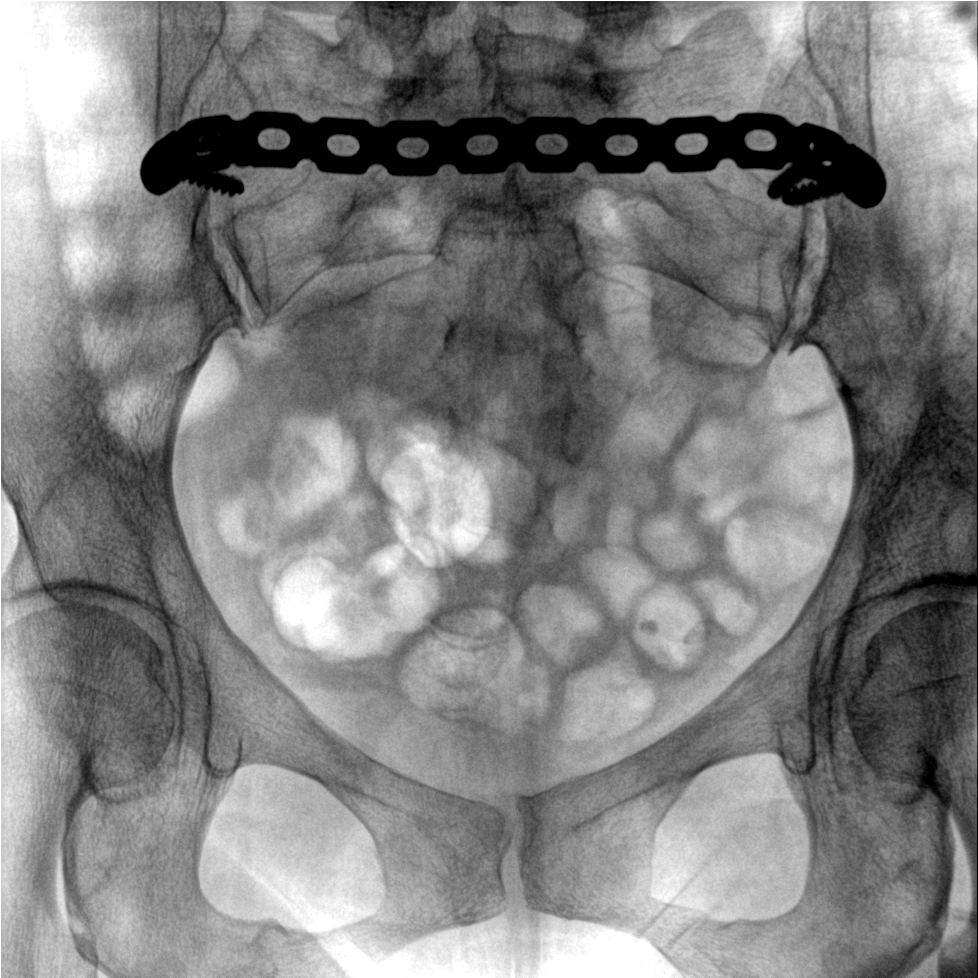

術中三維成像和橫斷面圖像提供多角度的手術診斷信息,輔助醫生進行術中評估判斷,諸如骨折復位情況和內植入螺釘的尺寸和位置,輔助手術更好地完成。

提供更大的術中三維成像視野,采集更多圖像信息,可一次拍全全段頸椎、全段腰椎、七節胸椎、雙側骶髂關節、股骨頭及單側盆骨。